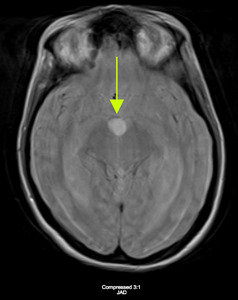

Considerations were given to possible adverse drug reaction to Promethazine, other toxic or infectious etiologies, or structural lesions. Laboratory studies were within normal limits. While waiting to receive a CT scan of her brain, a bedside ocular ultrasound was performed which demonstrated an optic nerve sheath diameter less than 5 mm. without evidence of papilledema. Her CT brain without IV contrast demonstrated dilated lateral ventricles with associated transependymal edema. (Figure 1) An emergent MRI of the brain without contrast was completed to identify a colloid cyst at the level of the Foramen of Monro measuring 1.3 x 1.3 cm. (Figure 2) There was marked obstructive hydrocephalus and cerebral sulcal effacement seen in the image consistent with cerebral edema. The patient was admitted to our hospital for evaluation by the Neurology and Neurosurgery teams.

Imaging studies are essential in the workup of patients presenting with symptoms suggestive of possible hydrocephalus. A CT brain without contrast is the initial test of choice. Approximately 2/3 of colloid cysts appear hyperdense on imaging. The lesions are usually round or ovoid and are well delineated. Most cysts range between 5-25 mm.10 The appearance of colloid cysts on MRI is important for neurosurgeons, because the surgical success rate is lower in colloid cysts that have decreased MRI T2-signal intensity.11 It is also important to keep in mind that lumbar puncture can be fatal as non-draining obstructive hydrocephalus can lead to herniation. An ophthalmologic evaluation may be useful if diplopia is a presenting complaint or if papilledema is found on physical examination as this may be a marker for increased ICP.9